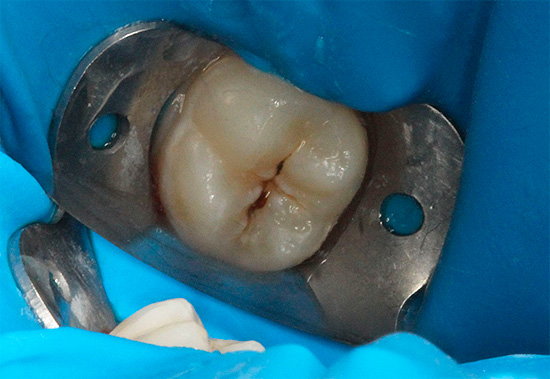

Ora vediamo cosa fare con il mal di denti con la pulpite.

Nella pulpite acuta, il fascio neurovascolare all'interno del dente subisce cambiamenti catastrofici. L'infiammazione dovuta all'azione dei microbi e delle loro tossine sul tessuto vivente del "nervo" provoca edema e graduale necrosi.

Non è difficile da immaginare: la polpa inizia gradualmente a "gonfiarsi", aumentando di dimensioni, e quando la camera della polpa non viene aperta, preme fortemente contro le pareti interne. Le terminazioni nervose sono compresse e si verifica dolore acuto, che può essere alleviato solo da forti antidolorifici.

Pertanto, nella maggior parte dei casi con pulpite, sarà richiesto un trattamento canalare, cioè un semplice riempimento non sarà sufficiente qui.